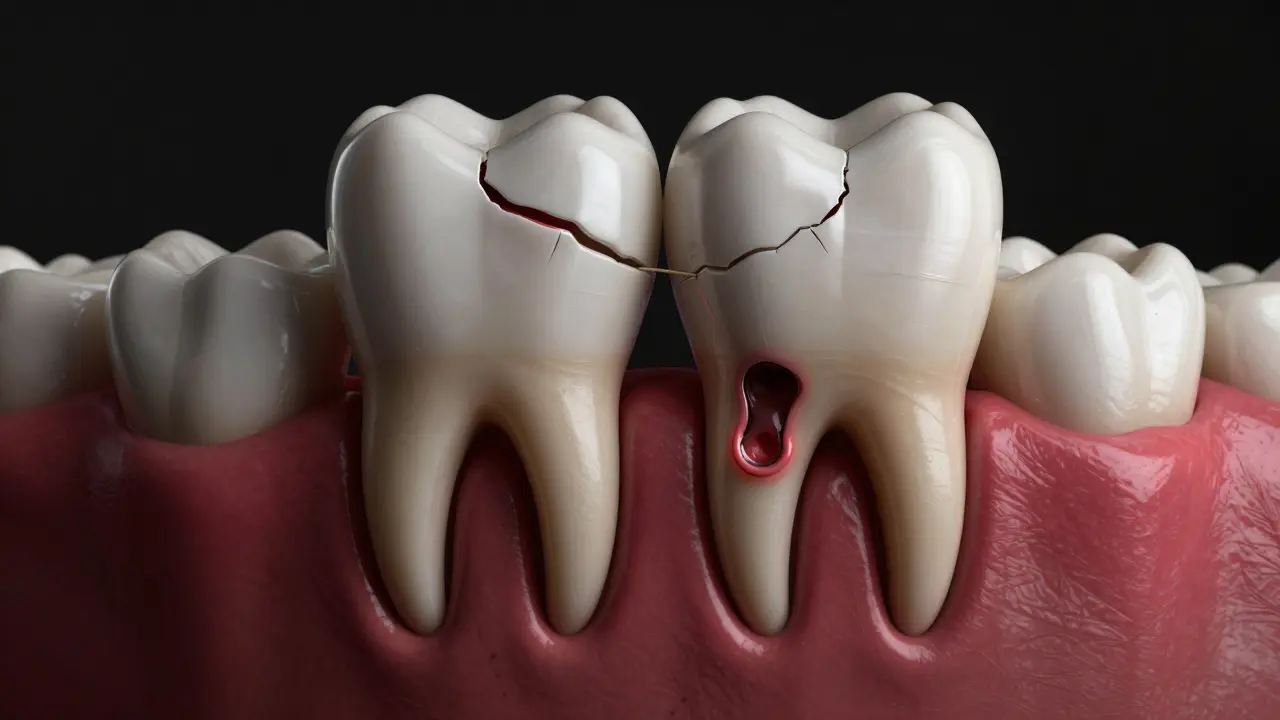

Cysta a poškozené zuby v čelisti

• Cysty nebo tumor v oblasti čelisti

• Poškození sousedních zubů (sedmiček)

• Stálé infekce a záněty dásní

• Křivost zubů v důsledku tlačení osmiček na ostatní zuby

Mezi nejčastější problémy patří poškození druhého moláru. Osmičky tlačí na něj, což může způsobit rozpad nebo nutnost jeho odstranění. V extrémních případech může dojít i k poškození nervů v čelisti, což může vést k trvalému brnění nebo necitlivosti v oblasti tváře.